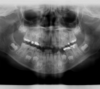

Vues avant le traitement à l'âge de 6 ans

Les radios avant le traitement